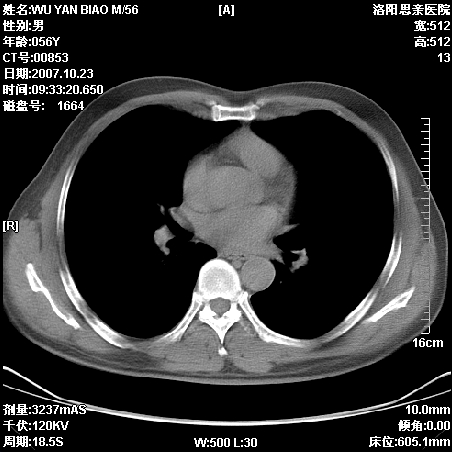

标题: CT10160:M56Y,体检发现,病人无不适,病人随访中 [打印本页]

标题: CT10160:M56Y,体检发现,病人无不适,病人随访中

后上纵隔占位,与肺交界清,宽基底附着脊柱,密度均匀,局部骨质无明确改变.

考虑;神经源性肿瘤,---起源交感n链?,不除外肠源性囊肿.

1、病灶在后纵隔脊柱旁沟内,此处是神经原性肿瘤的好发部位

2、病灶边缘光滑整齐,更说明病灶来于纵隔,由于有胸膜的包裹所以才导致这么光滑的边缘

3、病灶内的密度均匀